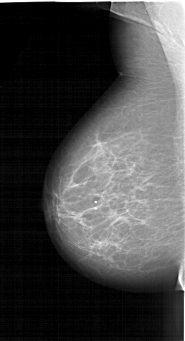

A_1264_1.LEFT_CC

LEFT_CC LINES 6106 PIXELS_PER_LINE 3376 BITS_PER_PIXEL 12 RESOLUTION 43.5 NON_OVERLAY